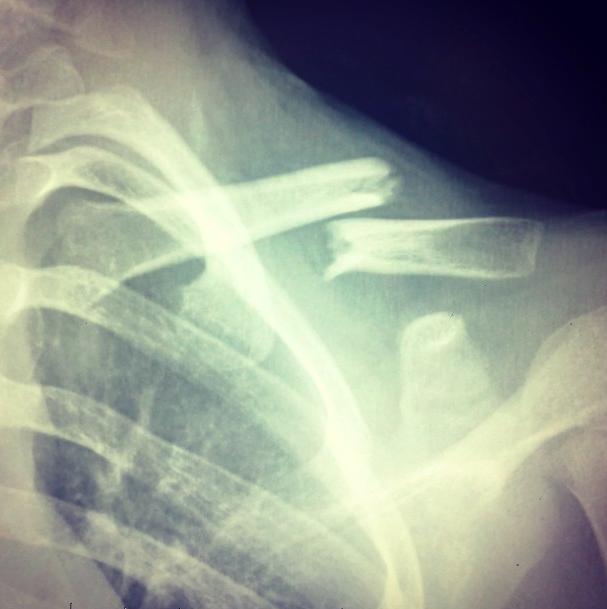

Liams-Xray-Collarbone by Shash August 29, 2015August 29, 2015Leave a Comment on Liams-Xray-Collarbone Share this... Facebook Twitter Linkedin Pinterest